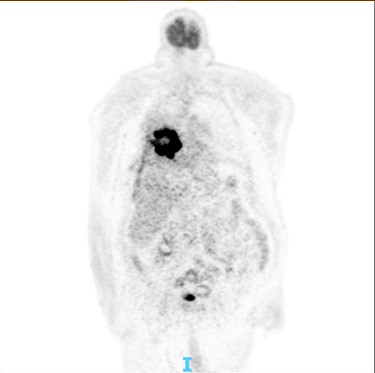

The post-operative recovery was uncomplicated, and the patient was discharged 7 days after the operation, with aim to start chemotherapy for the lung malignancy. After his discharge, a positron emission tomography (PET) CT scan was conducted in order to give more information about his disseminated lymphoma, without any obvious FDG avid nodal or distant metastasis (Fig. 4). However, the patient passed away 2 months later due to multiorgan failure.

PET scan: there is no obvious cervical, supraclavicular, mediastinal, hilar and axillary lymphadenopathy.